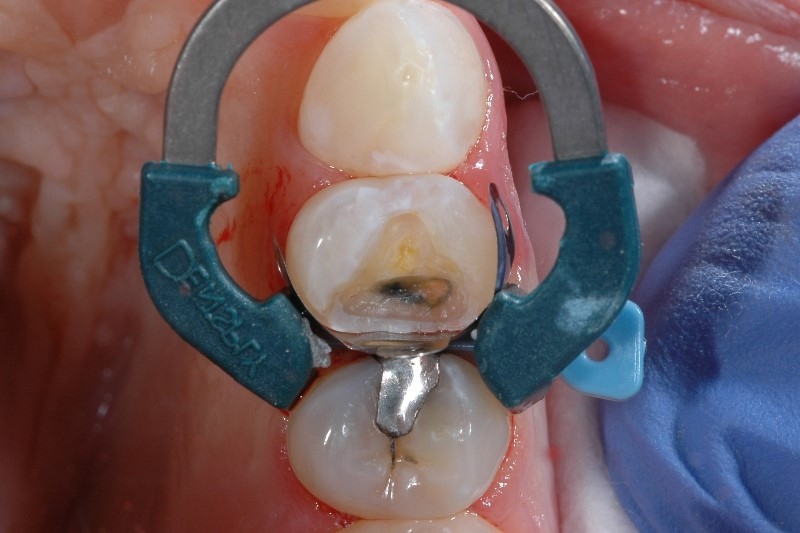

Sensibilité causée par une mauvaise isolation des dents

Une bonne isolation des dents est essentielle durant toutes les phases de restauration de classe II, car celle-ci empêche la salive et le sang de contaminer le champ de restauration. Si le champ de restauration est contaminé, les propriétés physiques et le succès final de la restauration composite peuvent être compromis, entraînant une sensibilité post-opératoire et une gêne pour le patient.

Comment éviter la sensibilité causée par une mauvaise isolation des dents

Si vous rencontrez des difficultés avec l'isolement, vous n'êtes pas seul. 97 % des cliniciens rapportent qu'il est difficile d'obtenir un isolement correct d'une cavité de classe II dans au moins 1 cas sur 10.2 Outre les mesures courantes d'isolement, considérez l'importance d'une matrice bien adaptée. L’utilisation de systèmes de matrice développés spécifiquement pour la mise en place de matériaux composites, comme notre système de matrice sectionnelle Palodent® V3 Sectional Matrix System, aide à obtenir un joint étanche au niveau de la marge gingivale.